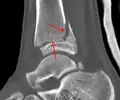

CT

CT scans may be indicated when there is concern for a highly comminuted fracture or a fracture involving the joint surface.[9] This imaging may be used for surgical planning.